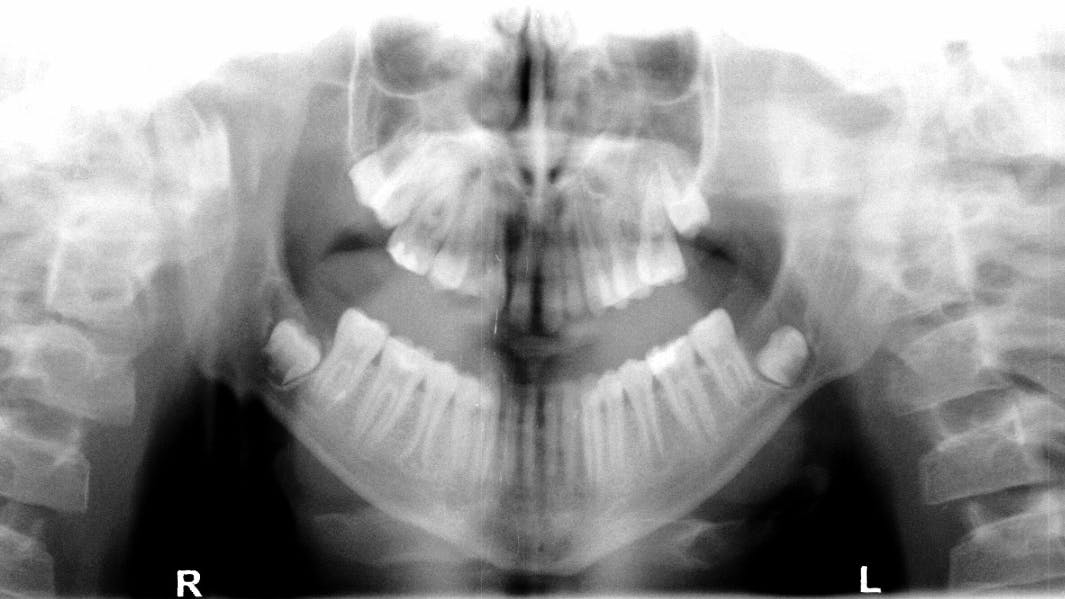

Figure 2: 6 mm x 9 mm irregular-shaped lesion appears white

Pathology case Dx: The lesion that many of our patients have

A leukoplakic lesion is one of the most common skin lesions that develops primarily due to cumulative sun exposure. Here, a patient presents with a lesion on the lower lip.